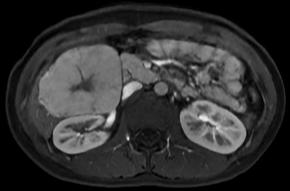

• Portal venous phase image

Comments This case report describes a hepatic tumor that was incidentally discovered in a pediatric patient with no underlying liver disease. On color Doppler imaging, there were findings suggestive of a central stellate scar, and the corresponding area demonstrated high signal intensity on T2-weighted MRI. Furthermore, on contrast-enhanced MRI, the lesion, excluding the central scar, showed homogeneous enhancement during the arterial phase and persistent enhancement in the portal venous phase with no evidence of washout. An additional finding, though not presented in the primary text, was homogeneous high signal intensity in the hepatobiliary phase (sparing the central scar). All of these findings are characteristic of focal nodular hyperplasia.